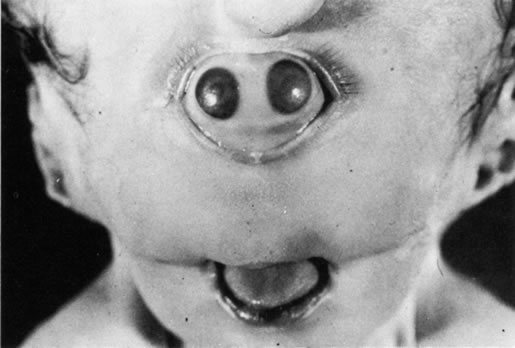

Anophthalmos and microphthalmos are usually unilateral and may be associated with a variety of craniofacial and systemic anomalies, including orbital hypoplasia, facial clefts, basal encephalocele, hemifacial microsomia, mandibulofacial dysostosis, cardiac anomalies, polydactyly, and mental retardation. When they occur unilaterally, they also can be associated with anomalies of the contralateral “normal” eye, including cataract, cornea1 opacities, microphthalmos, coloboma, epibulbar dermoids, and nystagmus. Anophthalmos and severe microphthalmos frequently are associated with contracted conjunctival fornices, phimotic eyelids, and generalized hypoplasia of the periocular soft tissues (Fig. 1). When soft tissue contractures occur, the early use of conformers is essential to expand these tissues.2 This treatment should be instituted in the first month of life, with progressive enlargement of the conformer over time to achieve maximum expansion of the conjunctival fornix. Unfortunately, this treatment usually does not stimulate adequate orbital bone growth, and unilateral microphthalmos and anophthalmos may be associated with secondary orbital hypoplasia (Fig. 2). Serial implantation of progressively larger orbital implants or placement of expansile orbital implants has been advocated to stimulate bony orbital development.3,4